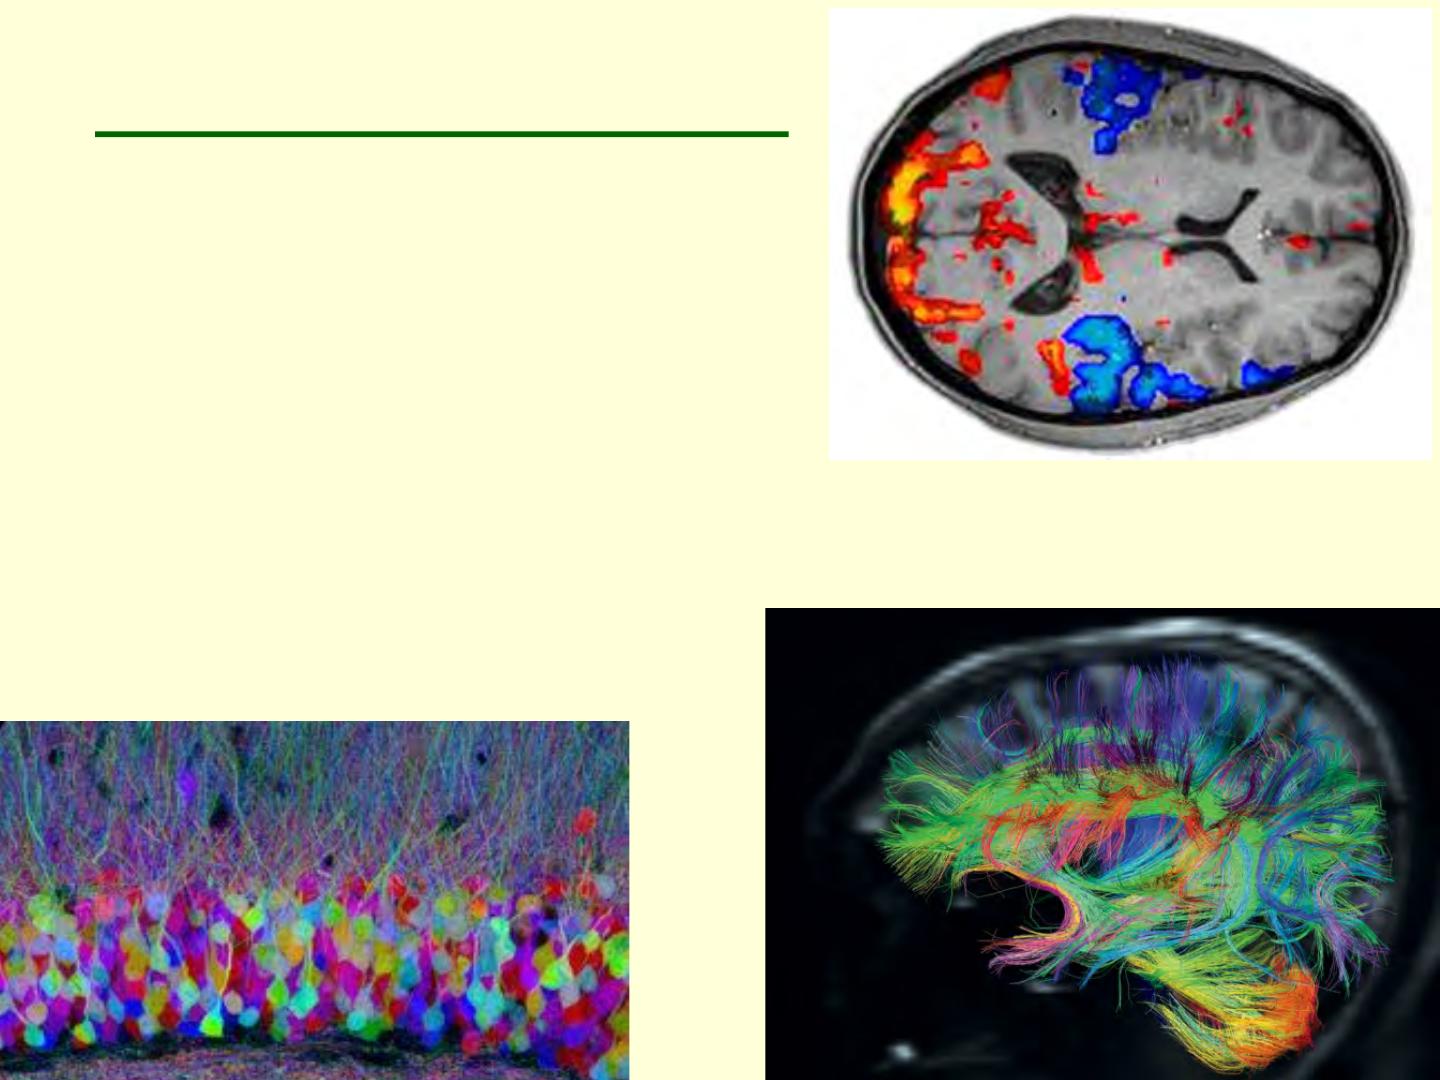

Voir le cerveau en couleur

pour le cartographier

IRM de diffusion

Cartographier les réseaux fonctionnels

L’organisation générale de nos réseaux cérébraux